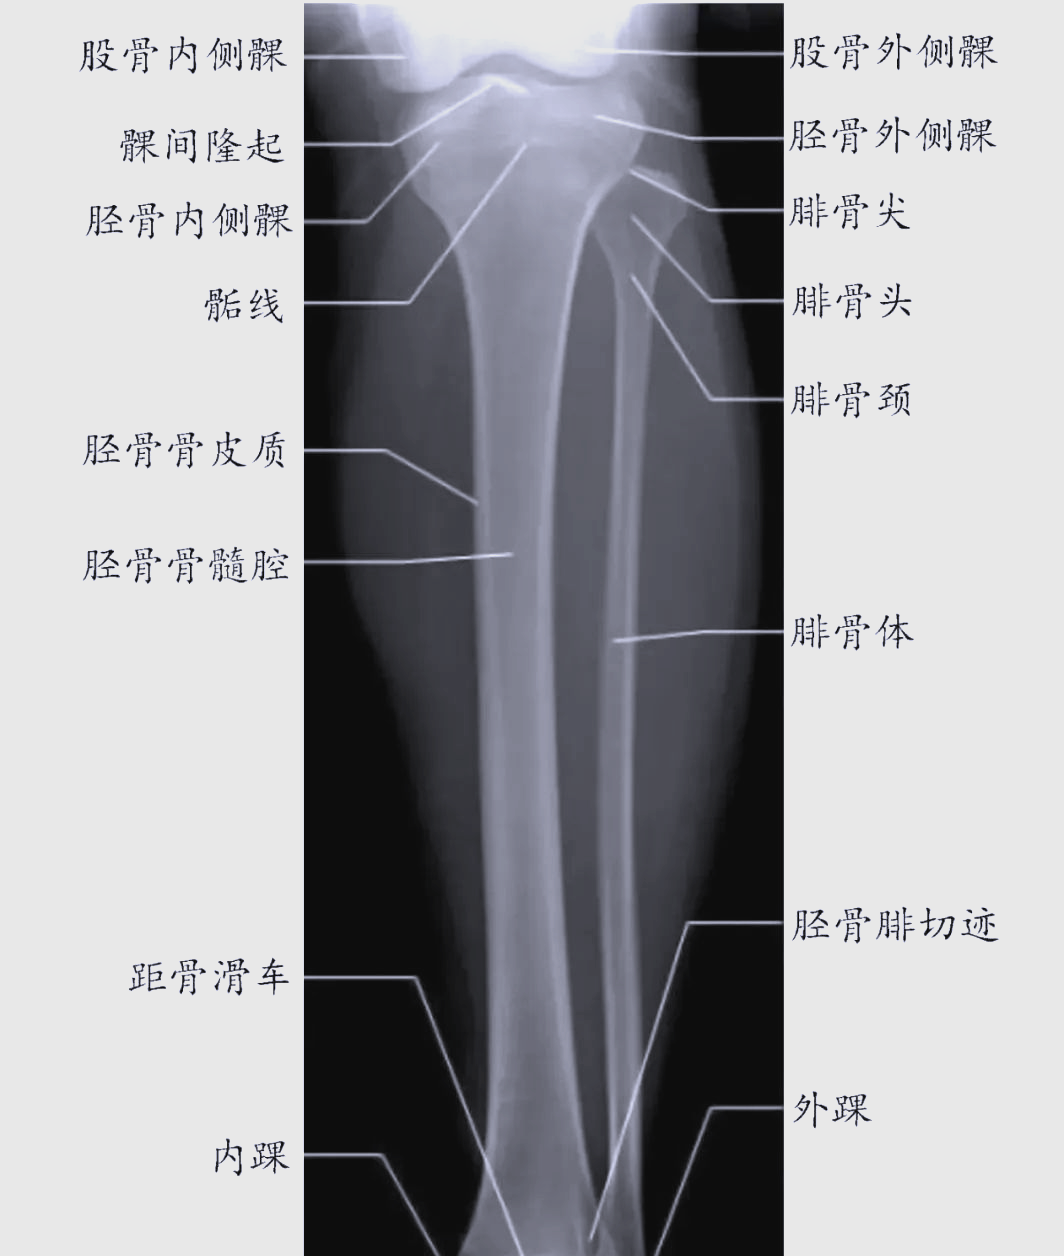

胫腓骨

每日一骨:腓骨的解剖结构详解 🦴

一文详细了解胫骨解剖特点